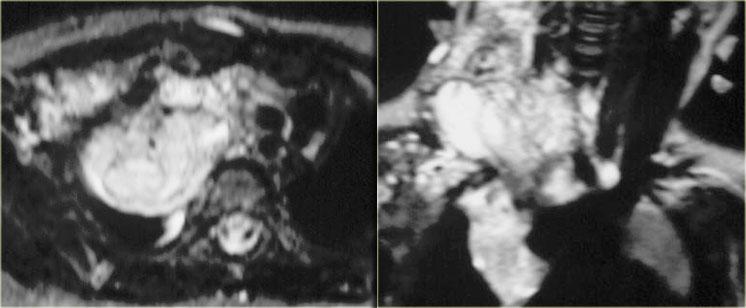

MRI đôi khi có thể được sử dụng để xác định rõ hơn sự lan rộng của tổn thương.

MRI ở bệnh nhân này cho thấy một khối nang ở cổ lan rộng vào hố nách phải và trung thất.

Khối u bao quanh các mạch máu.

Sự hiện diện của ngấm thuốc ở thành hoặc các vách ngăn bên trong gợi ý nhiễm trùng chồng lên hoặc thành phần u mạch máu.